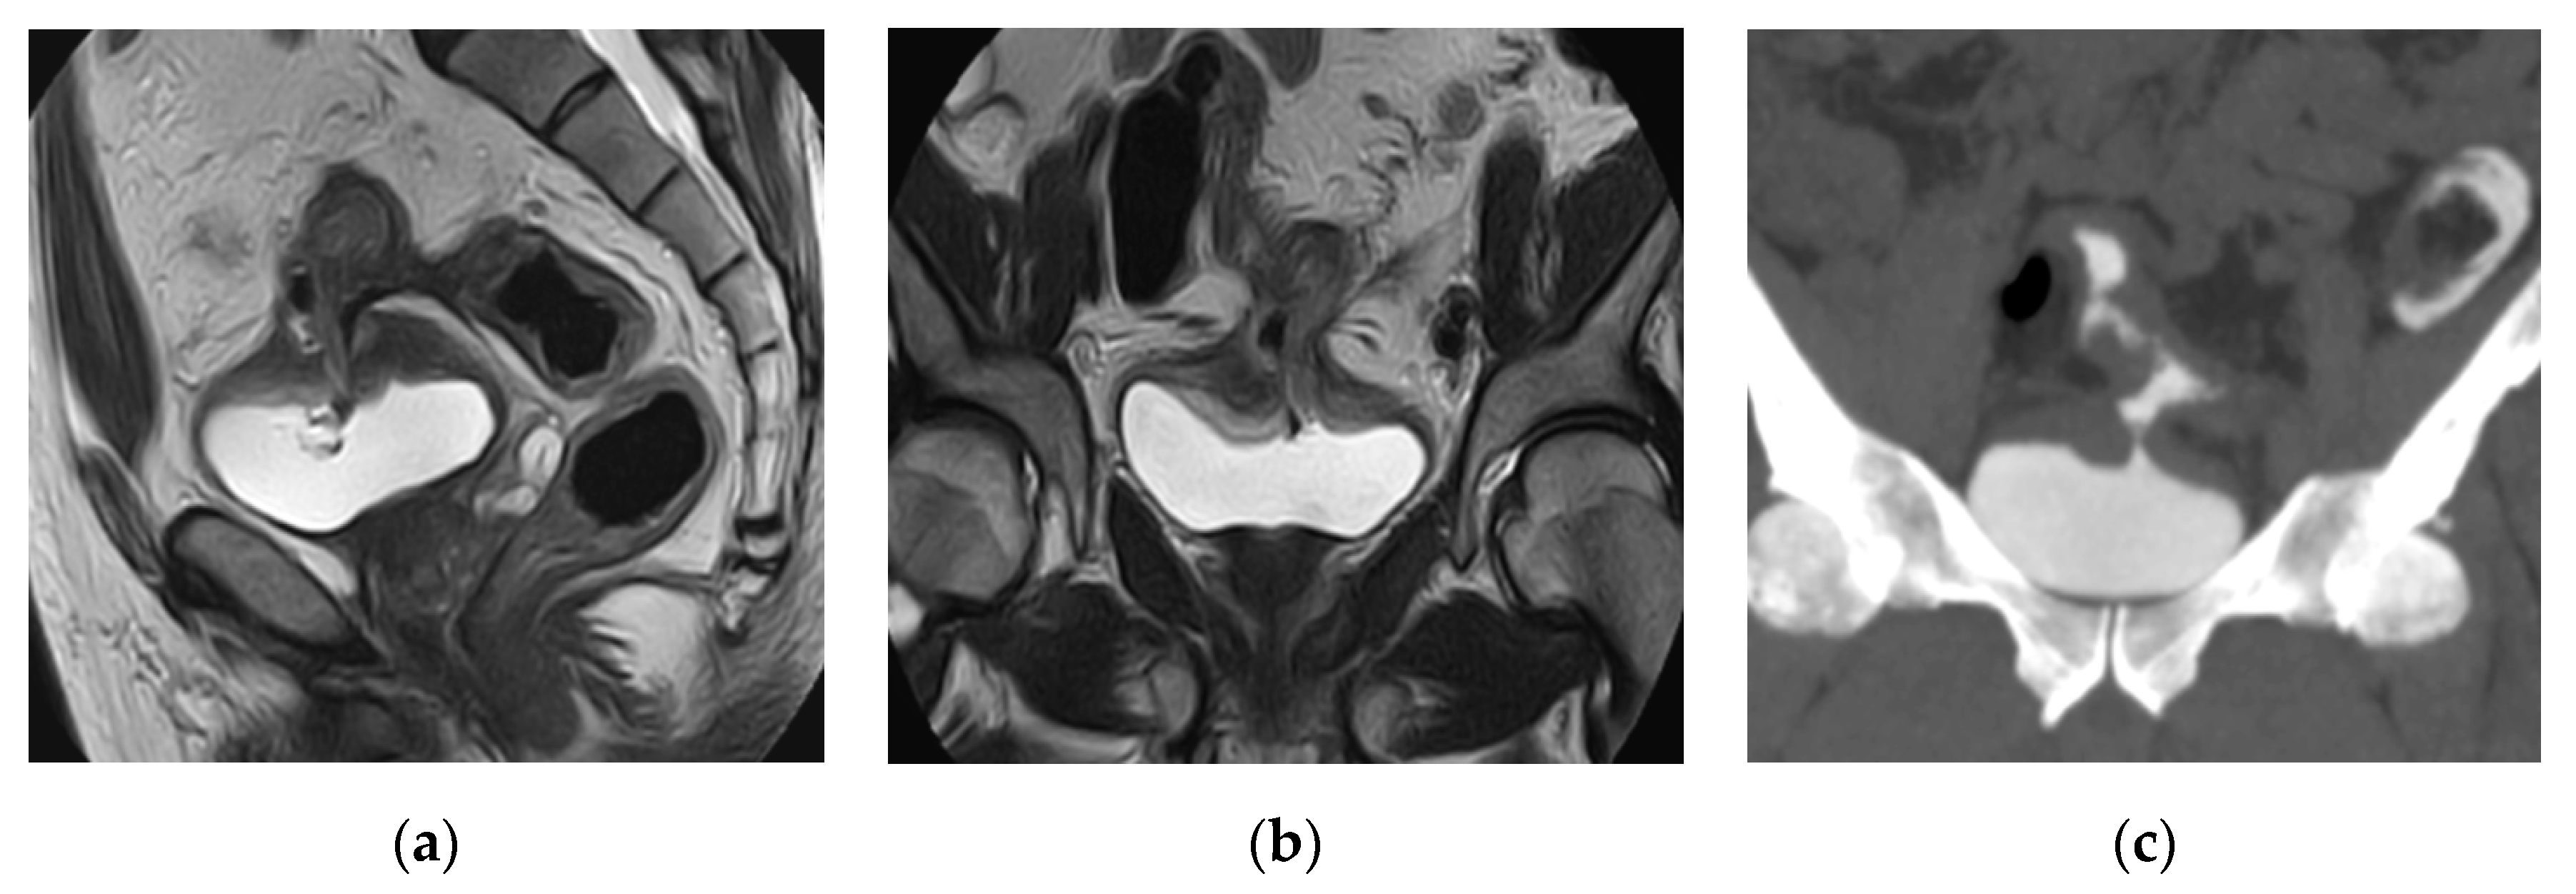

2.13. Eosinophilic Cystitis

| Acute infectious cystitis | Diffuse bladder wall thickening, especially if oedematous at T2 weighted image, urothelial hyperenhancement, perivesical fat stranding. |

| Mural bladder abscess | Intramural/exophytic non-enhancing fluid collection, irregular wall, often thick peripheral enhancement, usually affecting the upper bladder aspect. |